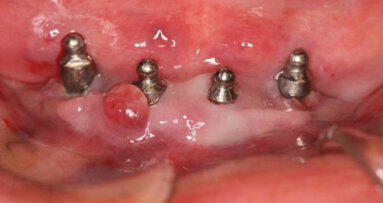

Un homme de 55 ans en bonne santé, se plaignait de mauvaise haleine et de saignements récurrents. L’examen clinique a montré un saignement au sondage (BOP) avec des profondeurs de poche au sondage (PPD) de 5 à 6 mm (Fig. 1), des dents stables sans mobilité, et l’exsudation. La radiographie a révélé une perte osseuse verticale et horizontale (Fig. 2). Par conséquent, ce cas a été classé en tant que parodontite sévère. L’hygiéniste dentaire a commencé le traitement avec un détartrage et surfaçage radiculaire, puis a montré au patient comment pratiquer une bonne hygiène buccale. Six semaines plus tard la situation a été réévaluée : il n’y avait eu aucune amélioration clinique significative ni des PPD ni du BOP. Nous avons décidé d’effectuer une intervention chirurgicale à lambeau ouvert.

Un système en option d’alimentation par bouteille a été intégré dans l’appareil, pour une alimentation en solution saline stérile pendant la chirurgie. Les incisions intrasulculaire, palatines et buccales ont été effectuées avec une pointe de 600 μm sous anesthésie locale (Fig. 3). Un jet d’eau a été utilisé pour le refroidissement des tissus, tout au long de la procédure par laser erbium. Une pointe de saphir de 600 μm a été utilisée avec 200 mJ/35 Hz (= 7 W) en mode contact, à une profondeur intrasulculaire. Après le soulèvement du lambeau (Fig. 4) le tissu granulé a été enlevé par ablation et vaporisation, en utilisant une pointe de 1 300 μm, en mode sans contact, à une distance de 1 à 1,5 mm du tissu cible (Fig. 5). L’énergie utilisée pour cette procédure était de 400 mJ/20 Hz (= 8 W). Dans les embrasures étroites, où la pointe était trop large, la pointe de 1 300 μm a été remplacée par une pointe conique plus étroite (800 μm) et l’énergie a été réduite. Puisque le laser est émis par l’extrémité de la pointe et non par ses côtés, même lorsque le côté de la pointe « s’appuie » sur une autre dent pendant la libération du laser, la dent adjacente ne subit aucun dommage.

Après l’ablation des tissus mous,2 le tissu dur a été traité : pour le remodelage osseux la puissance a été réglée à 300 mJ/20 Hz1, 2, 8 (= 7 W). La pointe la plus adaptée est une pointe saphir de 1 300 μm appliquée en mode sans contact.8, 14 Pour le lissage de l’os, l’énergie appliquée est de 150 mJ/50 Hz (= 7,5 W), pointe saphir de 1 300 μm, en mode sans contact. Avant de fermer le lambeau l’énergie laser doit être appliquée sur les racines exposées en mode sans contact, sur les sites buccaux, palatins, et interproximaux à une énergie très faible de 100 mJ/35 Hz (= 3,5 W), en utilisant une pointe saphir de 1 300 μm en mode sans contact (Fig. 6).